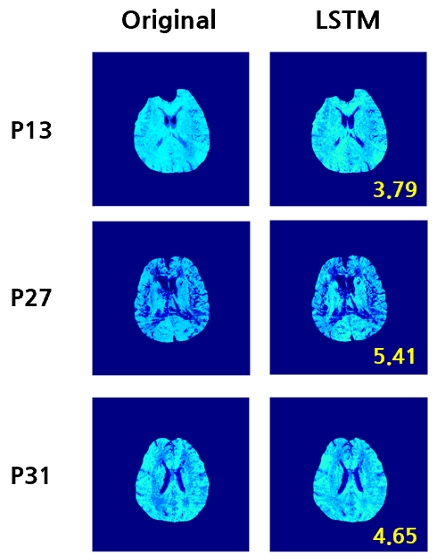

그림 4는 Ground Truth OEF 영상과 제안한 방법으로 추정한 OEF 영상을 시각적으로 비교한 결과를 도시하였다. 각 영상 우측에 표시된 노란색 숫자는 추정한 영상과 Ground Truth 간의 RMSE 값이다. 추정한 OEF 영상은 Ground Truth와 전반적으로 유사한 공간적 분포를 나타냈다. 이는 제안한 모델이 OEF 예측에서 유의미함을 시사한다.